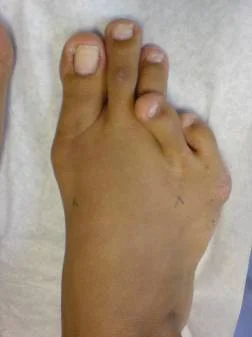

Hallux Valgus

Hallux valgus. Caso clínico:

Paciente femenino de 32 años de edad, quien consulto por dolor en pie derecho, secundario a hallux valgus por metatarso primo varo. Fue intervenida quirúrgicamente con excelentes resultados. Ver más.